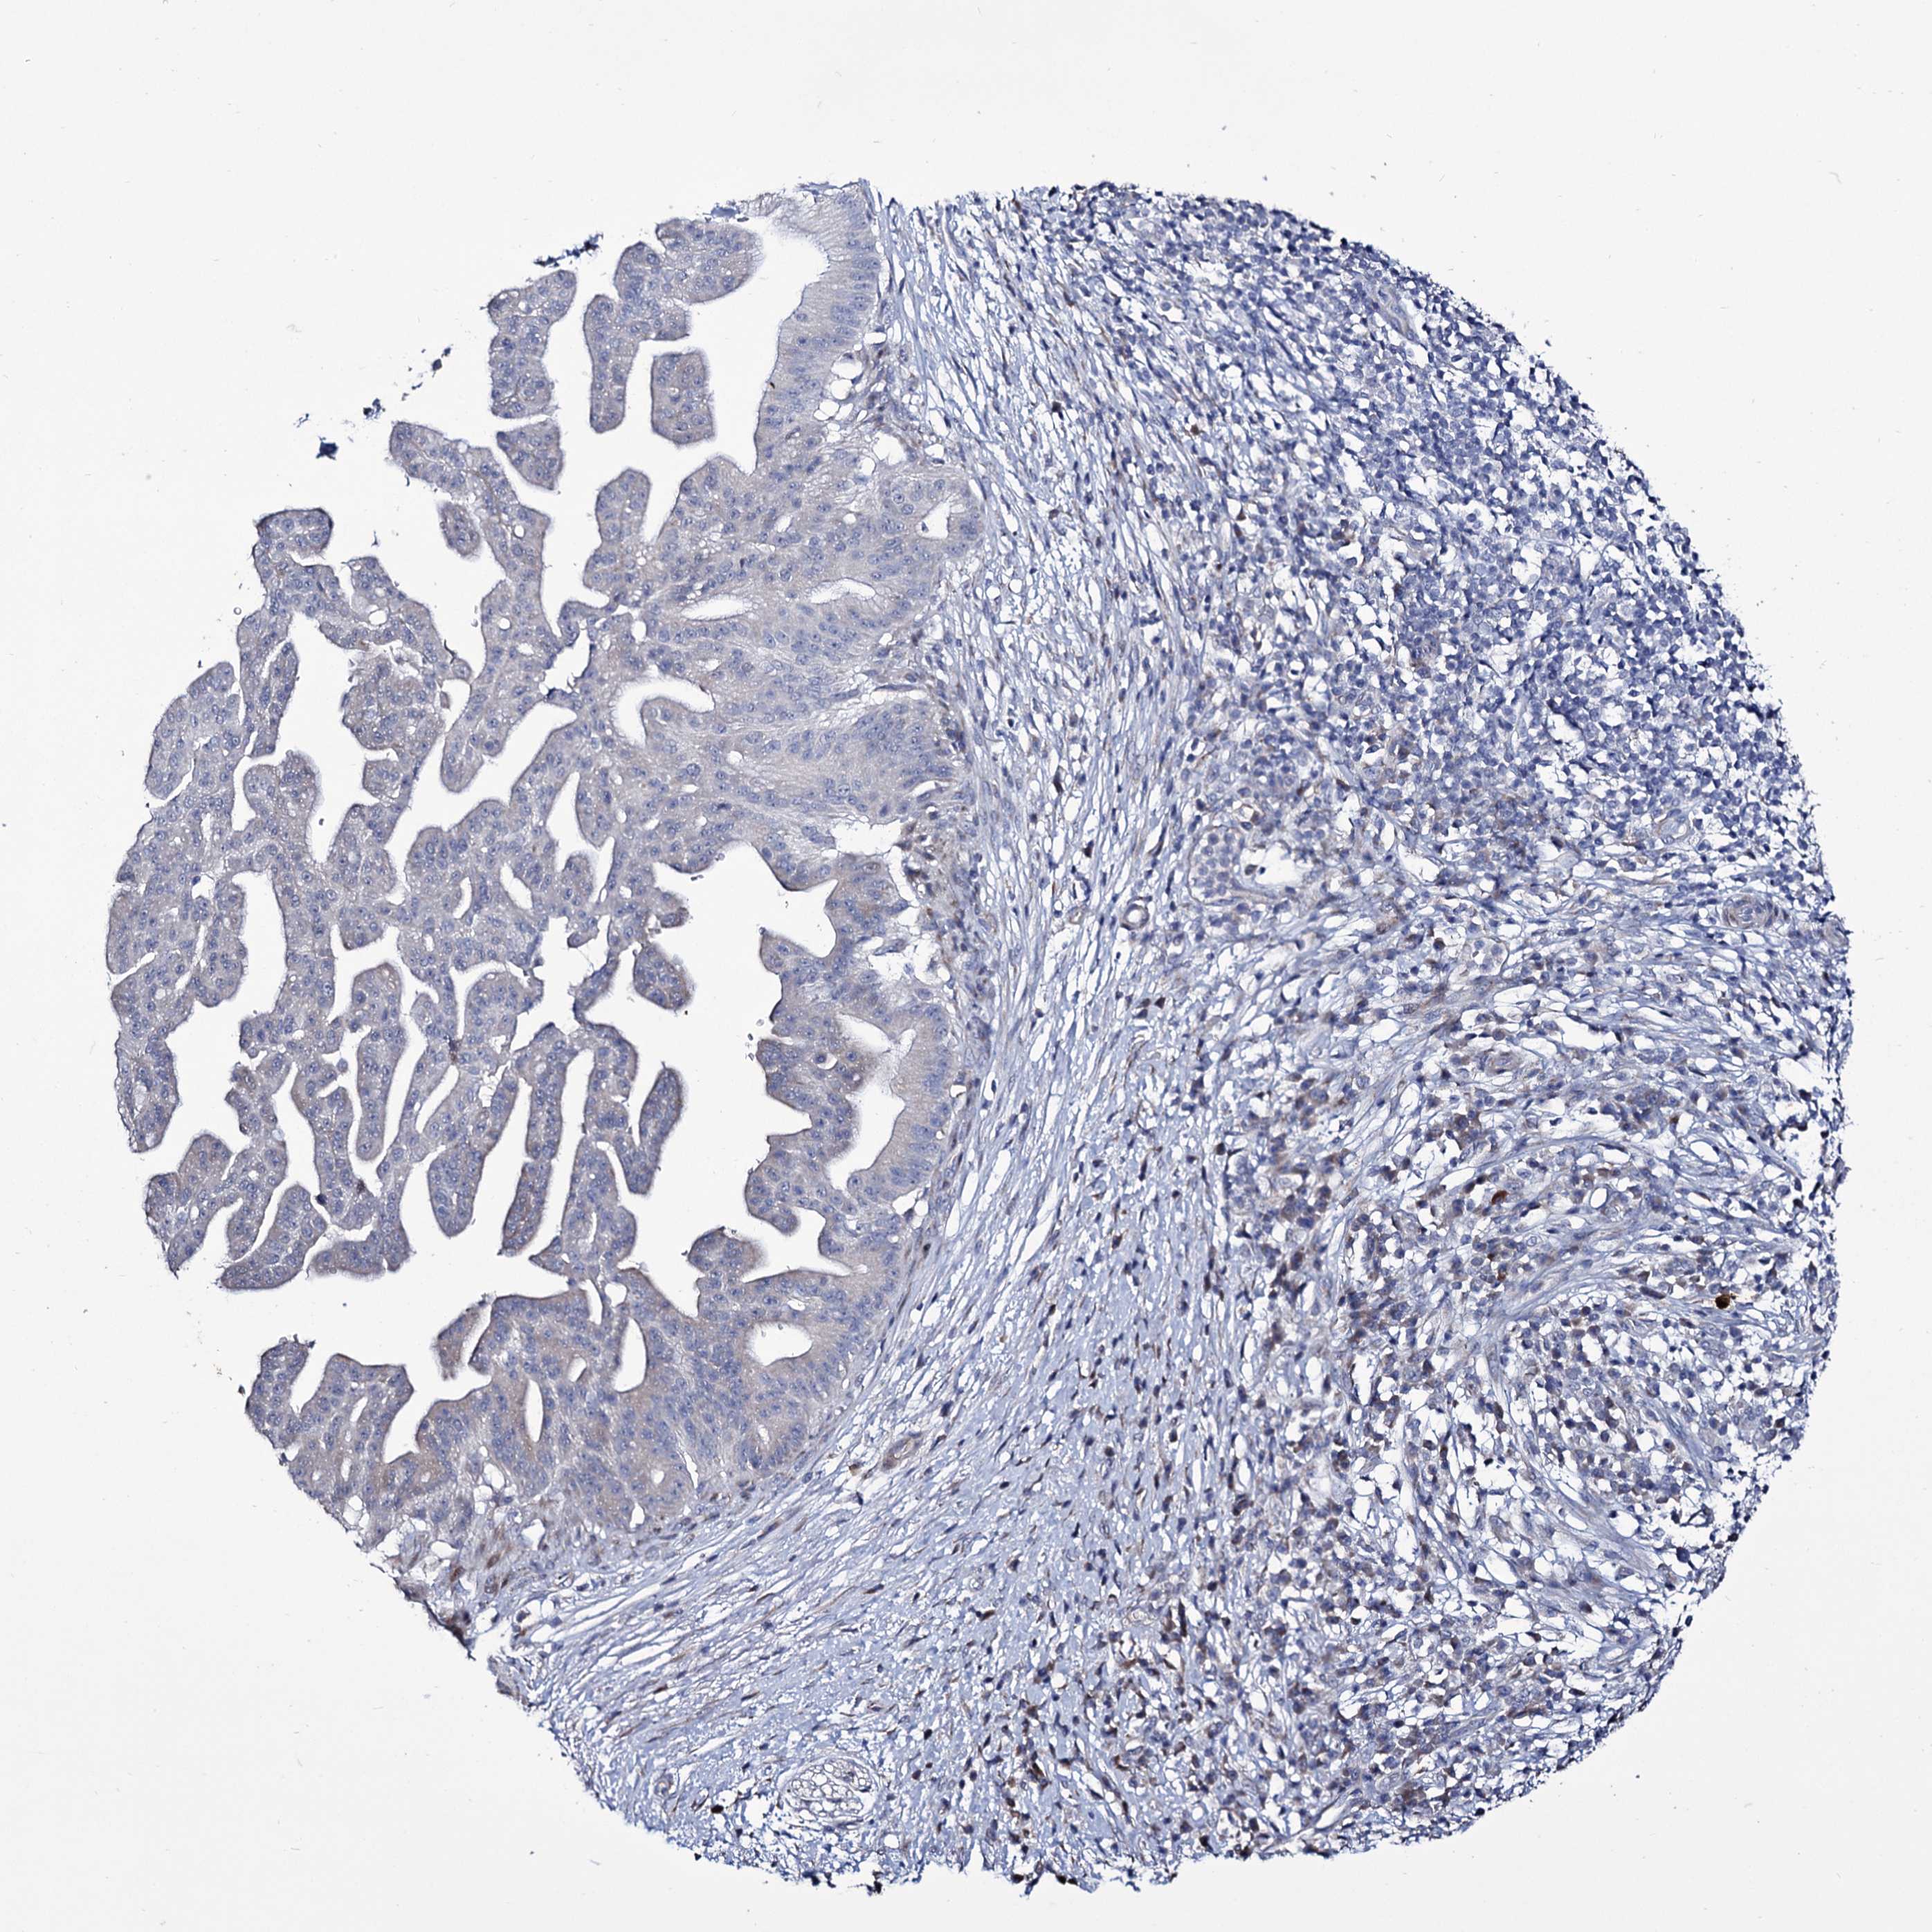

PANCREATIC CANCER - Protein expressioni

A mouse-over function shows sample information and annotation data. Click on an image to view it in a full screen mode. Samples can be filtered based on level of antibody staining by selecting one or several of the following categories: high, medium, low and not detected. The assay and annotation is described here.

Note that samples used for immunohistochemistry by the Human Protein Atlas do not correspond to samples in the TCGA dataset.

Antibody stainingi

Antibody staining in the annotated cell types in the current human tissue is reported as not detected, low, medium, or high, based on conventional immunohistochemistry profiling in selected tissues. This score is based on the combination of the staining intensity and fraction of stained cells.

Each image is clickable and will lead to virtual microscopy that enables deeper exploration of all samples and also displays staining intensity scores, fraction scores and subcellular localization as well as patient and tissue information for each sample.

Antibody HPA039366

Staining

High

Medium

Low

Not detected

Intensity

Strong

Moderate

Weak

Negative

Quantity

>75%

75%-25%

<25%

None

Location

Nuclear

Cytoplasmic/membranous

Cytoplasmic/membranous,nuclear

Adenocarcinoma, NOS